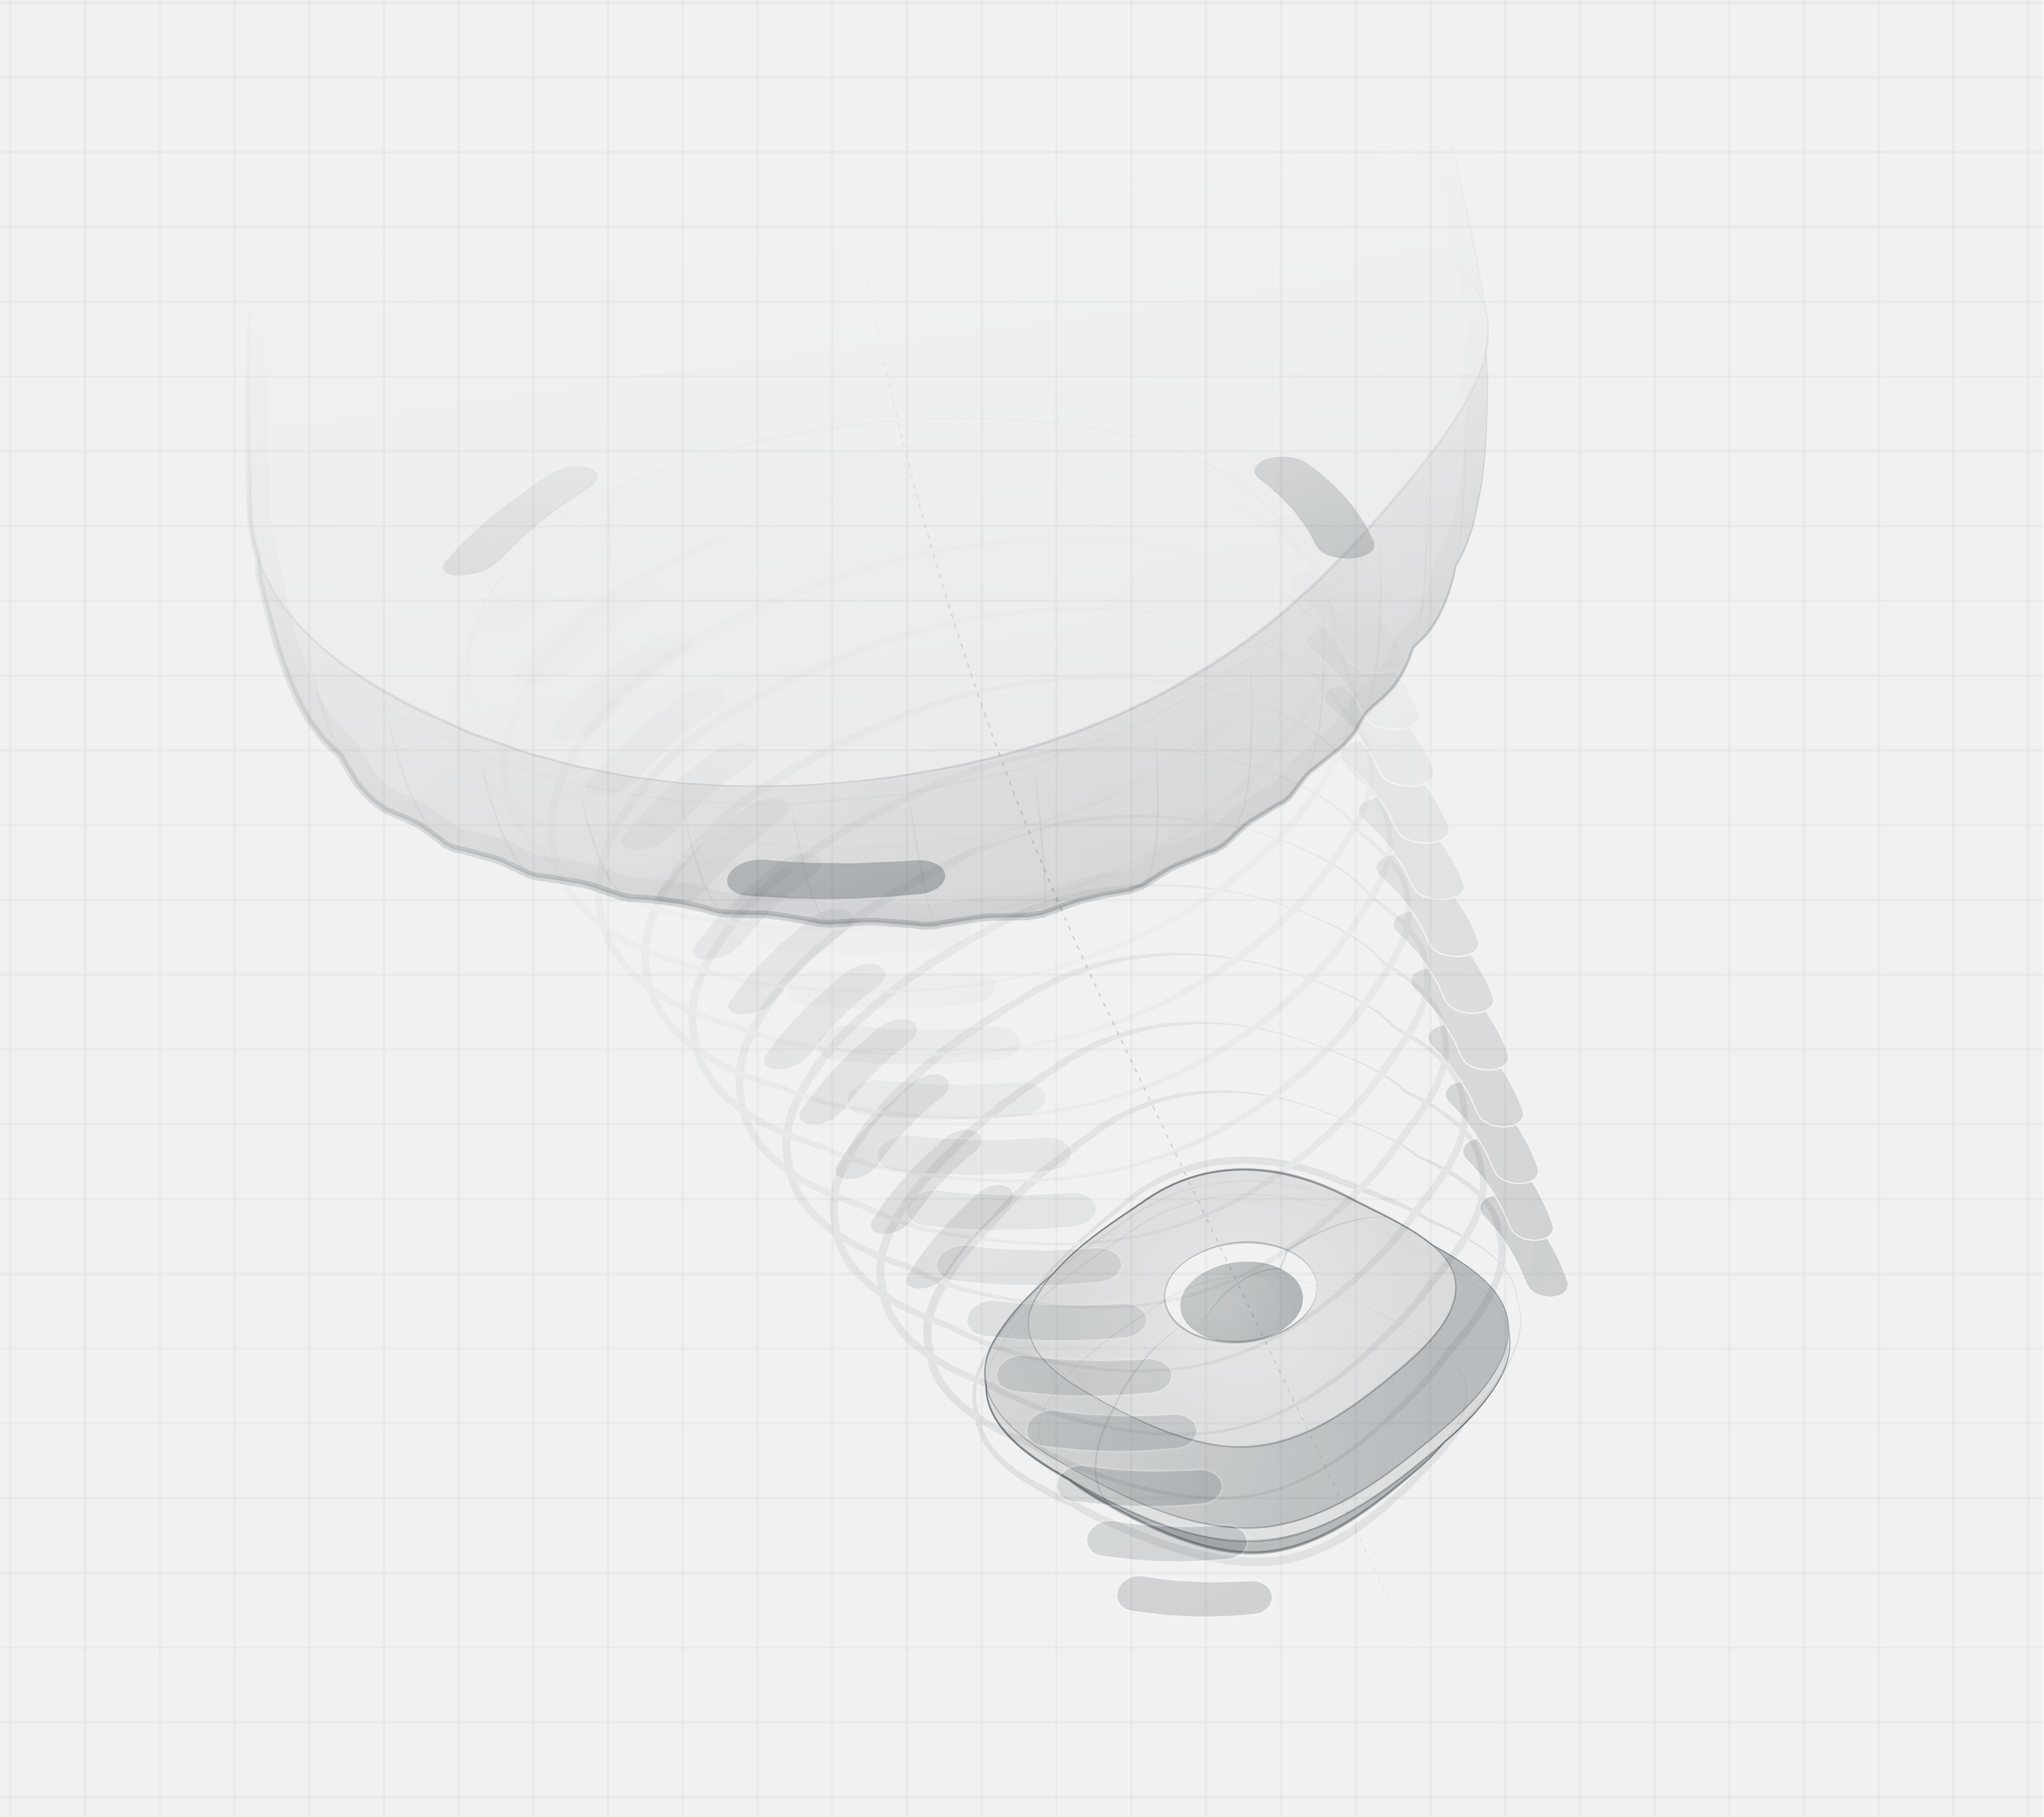

Ambulatory infusion pumps are notoriously complicated devices even for medical professionals. The FDA reported 710 deaths over a 5 year period linking many of which to human error. Robin provides automated workflows, intuitive feedback and reassurance for lay users and caregivers whilst maintaining flexibility and custom control for healthcare professionals.